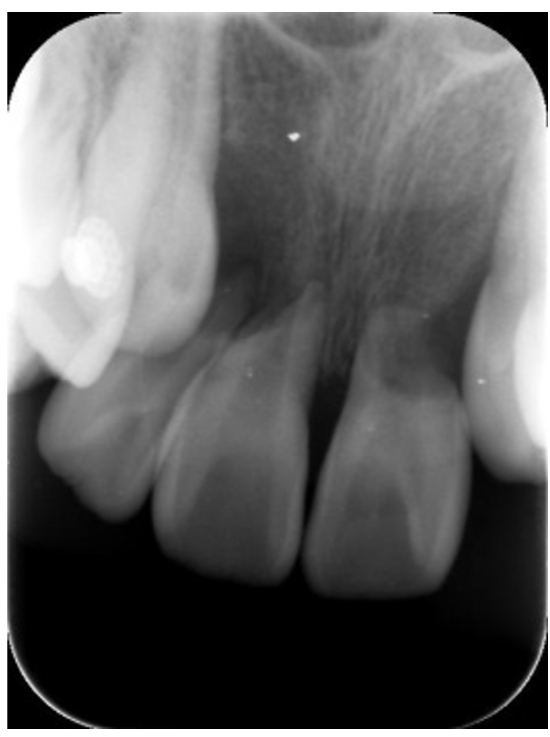

歯の根が短くなる“歯根吸収”とは?

レントゲンで「歯の根が少し短くなっています」と言われると、不安に感じる方も多いかもしれません。

この現象は“歯根吸収(しこんきゅうしゅう)”と呼ばれますが、実際にはほとんどの場合、問題になることはありません。

ごく一部のケースとして、子どもの頃に**犬歯が変な方向に埋まっている(埋伏犬歯)**場合、

前歯の根を圧迫して歯根吸収を起こすことがあります。

当院でもこれまで数症例だけ経験がありますが、

早期に発見して矯正治療で方向をコントロールすれば防ぐことが可能です。